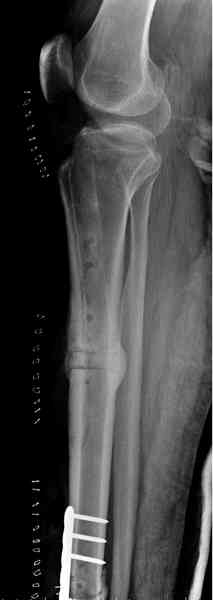

The diagnosis radiologically and post resection specimen coincides with typical osteofibrous dysplasia more than GCT.

I have some doubt about the diagnosis. Are you sure that this is a benign lesion? Has she pain? The age of the patient, specimen and X-rays don't exclude other more aggressive lesions. Do you have a preoperatory CT or NMR?

Yesterday our pathologist presented a preliminary conclusion - lytic GCT. Will pass specimens to colleagues from other facilities.

I spent my early orthopaedic surgical experience at an Italian bone tumor center. I have seen many GCTs of the bone, but none is similar to that you presented. I hope that this is a my error, but

it, in my opinion, appears aggressive and strange in diaphyseal localization. It seems in some aspects similar to a teleangectatic osteosarcoma, a variant of osteosarcoma (characteristic gross appearance of telangiectatic osteosarcoma is a multi-cystic "bag of blood". Microscopically, telangiectatic osteosarcoma has large blood filled spaces and thin septation. Within the septa there is scanty osteoid production by the pleomorphic malignant cells. Giant cells are not rare)

Пока наш морфолог подтверждает гигантоклеточную опухоль, литическую форму. Препараты передали еще и в другие учреждения, пока информации оттуда нет.